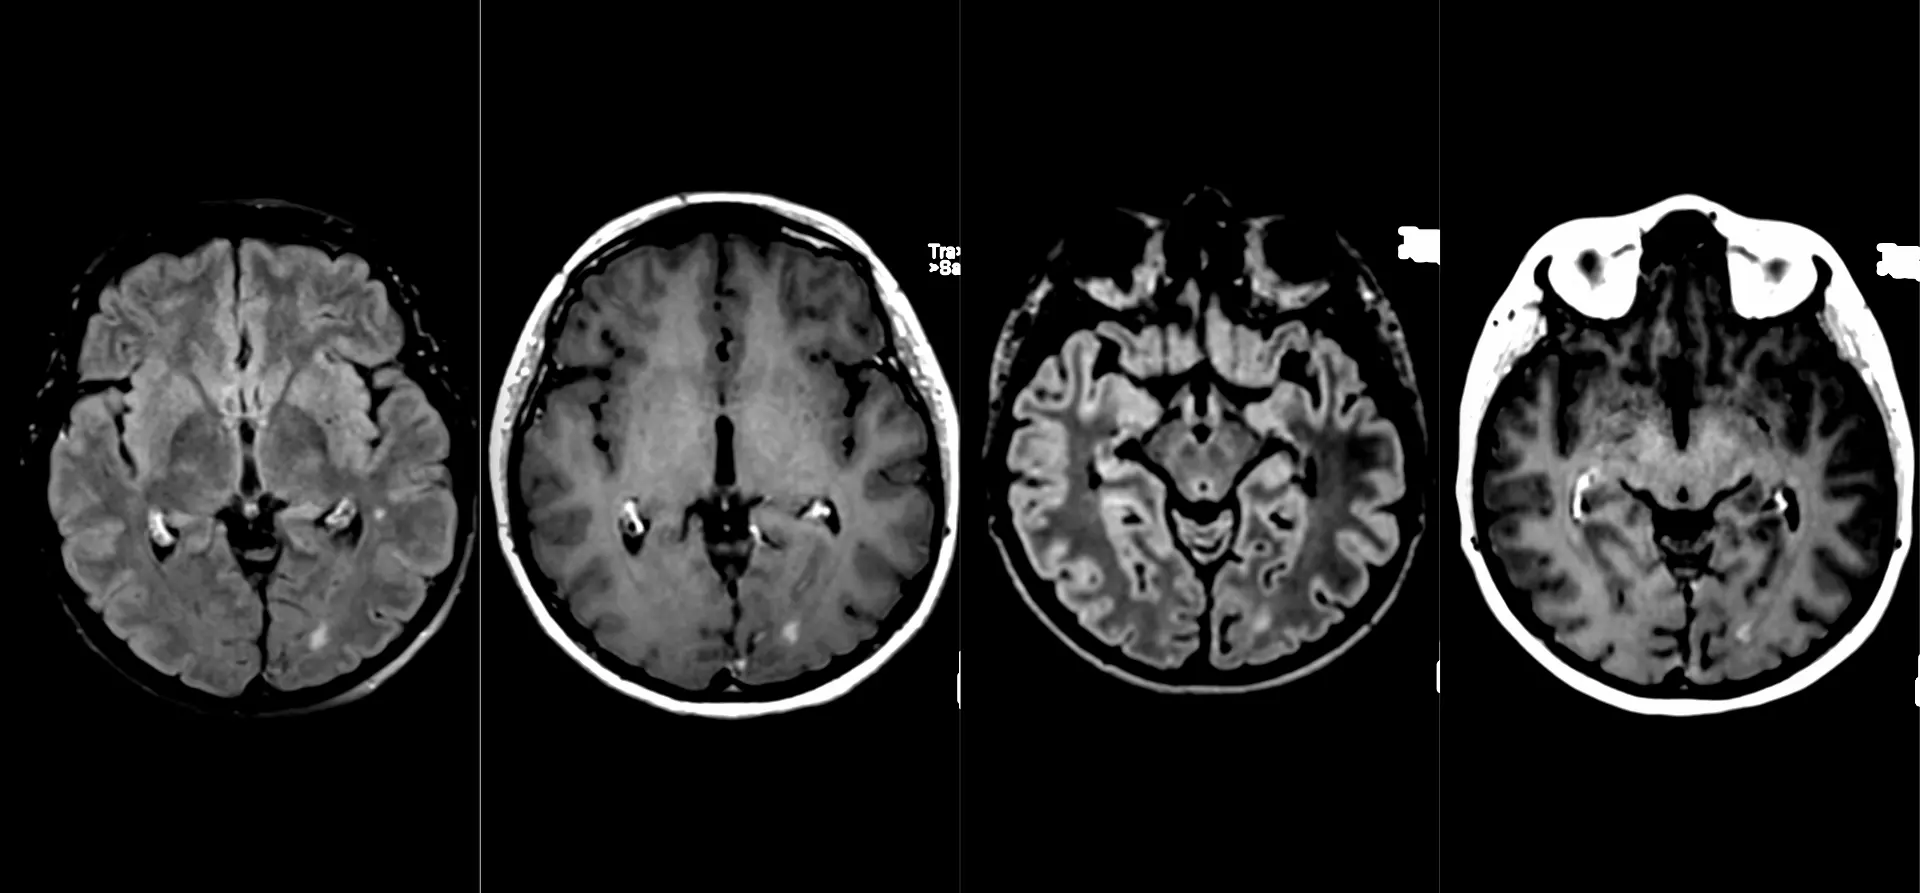

Женщина 32 года. Больной считает себя с 2024 г, когда стала отмечать онемение угла рта. Со слов пациентки ей был предварительно выставлен диагноз - РС, но дополнительных методов обследования и специфического лечения не проводилось. В настоящее время жалоб нет. В исследовании от октября 2024 отмечался очаг в левой затылочной доле с выраженным контрастированием, в настоящее время этот же очаг отмечается с сохраняющимся контрастированием. Формально - есть выполнение критериев диссеминации и в пространстве (юкстакортикальный и перивентрикулярный очаги есть), и во времени (есть усиливающиеся и неусиливающиеся очаги), клиника тоже вполне укладывается. Но! Найти в литературе подобных случаев мне не удалось, видел сам и максимум, что находил в литературе - полгода контрастирования. Получается, мы имеем дело с крайне атипичным рассеянным склерозом, или это не рассеянный склероз. А тогда что? Сосудистая мальформация не вариант - на SWI не видать. Какая-то ганглиоглиома? А другие очаги тогда что? Есть соображения? Кстати, диффузия стойко повышенная, и на б1000 почти не видно (изо). На Т2 не меняется